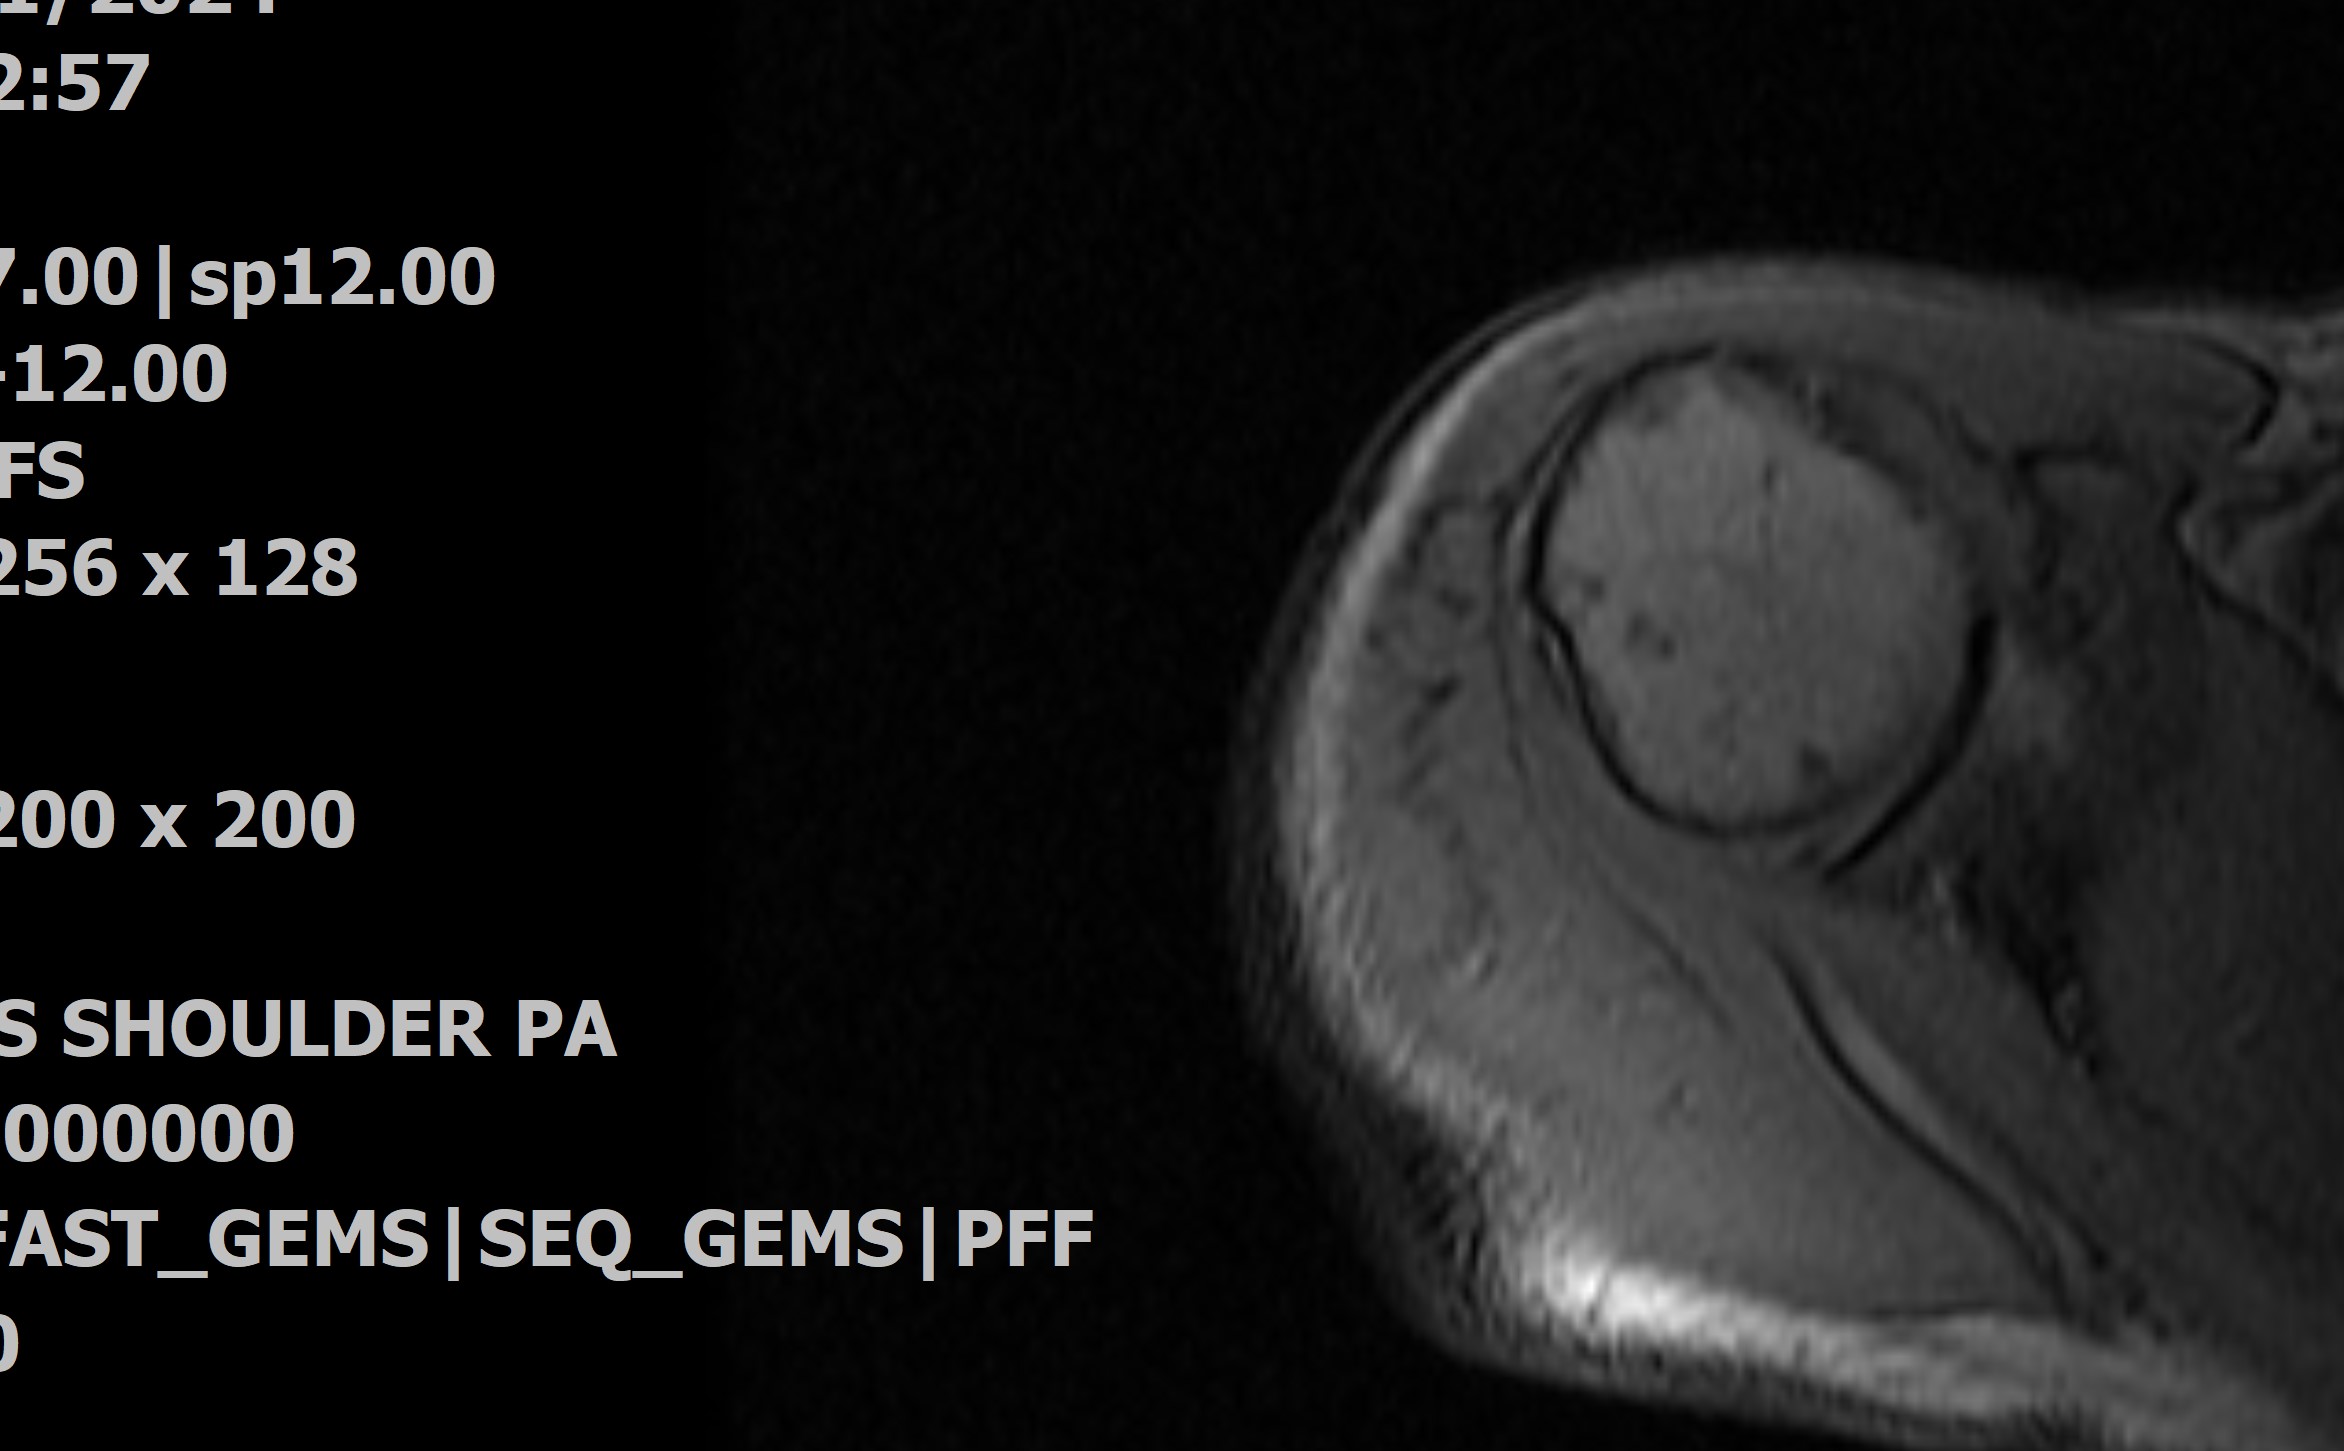

The MRI tube is ancient

as these scanners go, why I suppose

they can use it on me with my implant.

She rolls me into the tube after

my request, and as the machine

clangs to life I feel like a contestant